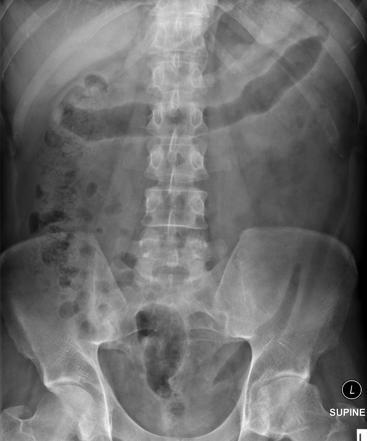

How can you distinguish the small bowel?

Mucosal folds = valvulae conniventes - seen across full width of bowel

How can you distinguish the large bowel?

Pouches that protrude into lumen = haustra

What are the spaces in between the haustra called?

Plicae semilunaris

What is the 3/6/9 rule?

Diameter of intestines should be no greater than:

3cm in small bowel

6cm for colon

9cm for caecum

What does thumb printing indicate + what is it?

Mucosal thickening of haustra due to IBD

What does a lead pipe colon indicate?

Loss of haustral markings secondary to chronic colitis